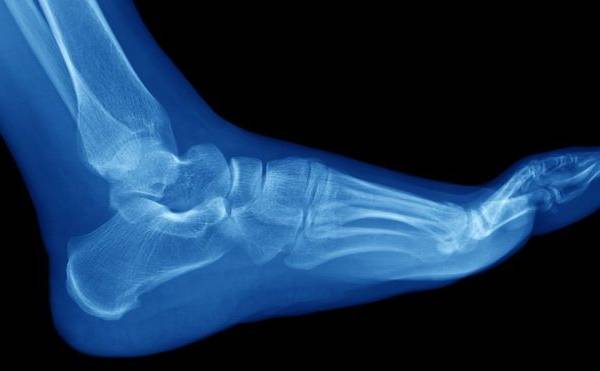

Las fracturas por estrés suelen ocurrir en los huesos de la parte inferior de la pierna y el pie

Las fracturas por estrés suelen ocurrir en los huesos de la parte inferior de la pierna.

Este tipo de roturas están normalmente asociadas al deporte y suelen ocurrir en los huesos de la parte inferior de la pierna y el pie, como la tibia y el peroné, los metatarsos, el talón y el tobillo.